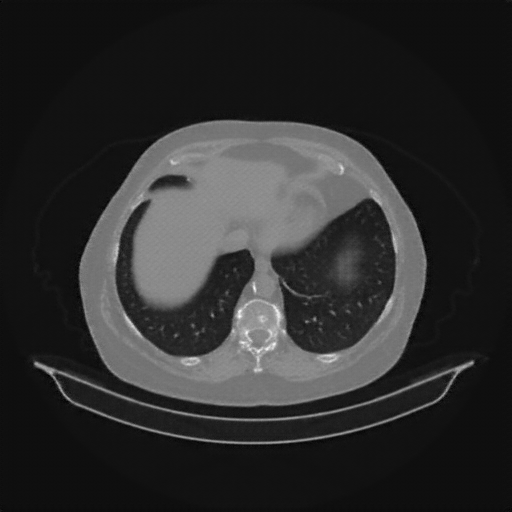

Generated VENOUS CT scan (A→B translation)

No window - Raw intensity values

Lung window (WL -600, WW 1500 β†’ Low βˆ’1350, High +150)

Mediastinum window (WL 40, WW 400 β†’ Low βˆ’160, High +240)